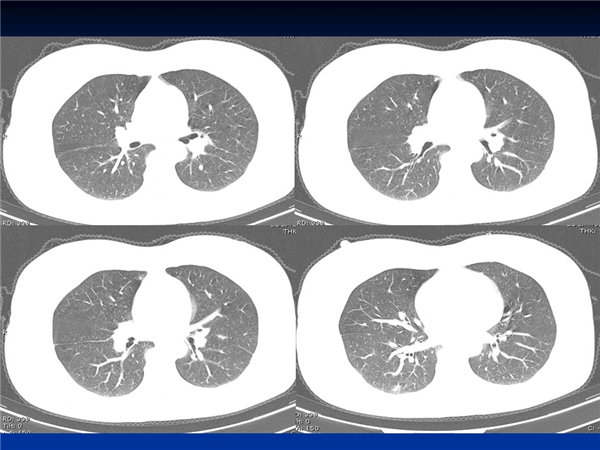

【病例分享】新型冠狀病毒感染肺部CT影像4例(常德市第一人民醫(yī)院)